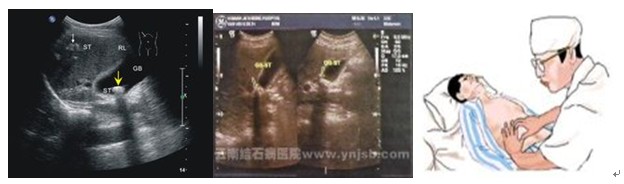

肝超声波检查和心电图有异常改变。